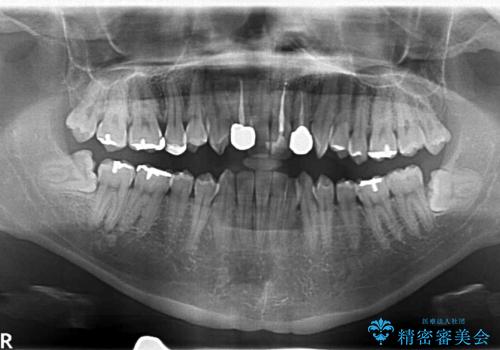

- 親知らず抜歯をしたいが、恐怖心が強く、静脈内鎮静(リラックス麻酔)下での施術を希望され来院されました。

静脈内鎮静法は、ほとんど記憶のないうちに手術を終えることを可能にする麻酔法になります。